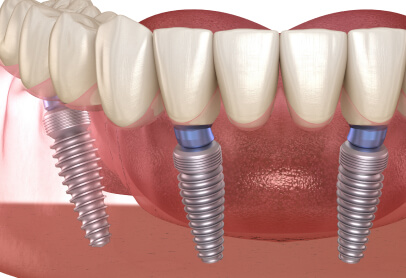

インプラントは失った歯の機能を取り戻す優れた治療法ですが、外科手術を伴うため、副作用について不安を感じる方も少なくありません。

「術後の痛みはどのくらい?」「顔が腫れたらどうしよう…」その不安、正しい知識で解消できます。このページでは、インプラント治療で起こりうる副作用の具体的な症状と、ご自身でできる対処法、そして当院の不安解消への取り組みについて詳しくご説明します。